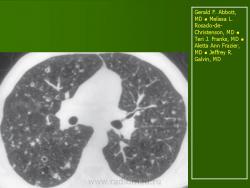

В 5 наблюдениях (21%) из больных с распространенной формой заболевания отмечались изменения в легких в виде обогащения, избыточности легочного рисунка, его деформации по сетчато-петлистому типу, очаговых теней. Корневая и медиастинальная аденопатия отсутствовали. В 1 случае в легких выявлена киста, которая периодически осложнялась нагноением (Рис. 4).

Поражение легочной ткани (рис. 22) свойственно любому возрасту. Часто больные имеют общие симптомы — лихорадку, слабость, реже — кашель, одышку, боли в грудной клетке. На рентгенограммах отмечается деформация и усиление легочного рисунка и микроузловые инфильтративные тени. Поражение костного мозга (с наличием клеток Лангерганса) сопровождается цитопенией периферической крови.

Рис. 22. Поражение легких при Лангер-гансово-клеточном гистиоцитозе.